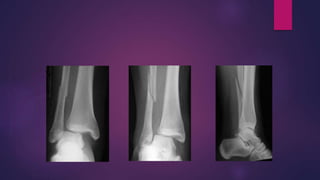

SUPINATION EXTERNAL ROTATION

SUPINATION ADDUCTION

PRONATION EXTERNAL ROTATION

(MAISSONEUVE’S INJURY)

(DUPUYTREN’S Fracture Dislocation)

PRONATION ABDUCTION